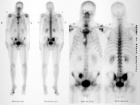

49 year old man with incidental finding on bone scan done after injury to his right toe

Zoom image: Radiological image Radiological image.